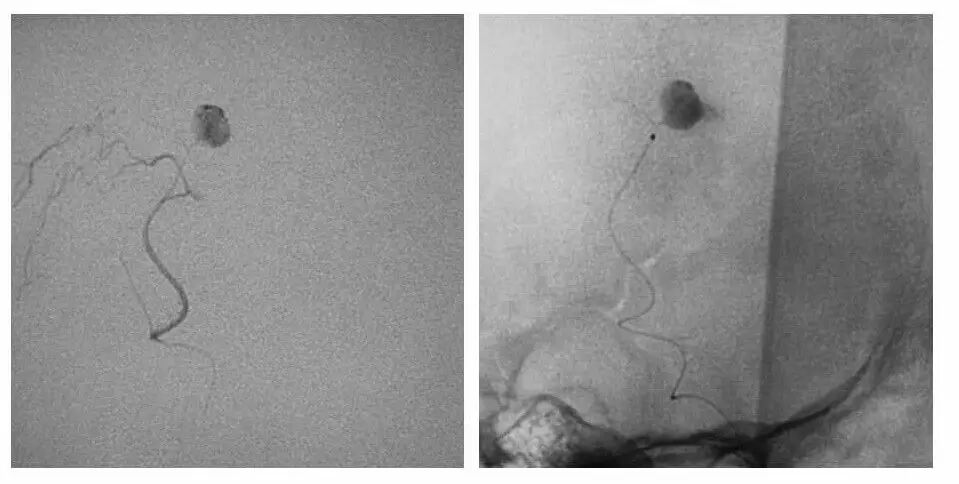

今天为大家分享的是“强生医疗CNV-神经介入专栏”第十五期,由首都医科大学宣武医院何川教授带来的“颅内动脉瘤介入治疗”精彩讲课视频及PPT,欢迎观看、阅读。文章仅代表作者个人观点,如有不同见解,欢迎同道斧正!